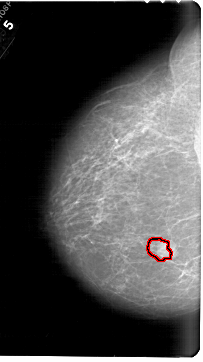

A_1567_1.RIGHT_MLO

RIGHT_MLO LINES 6871 PIXELS_PER_LINE 3781 BITS_PER_PIXEL 12 RESOLUTION 43.5 NON_OVERLAY

FILE: A_1567_1.LEFT_CC.OVERLAY

TOTAL_ABNORMALITIES 1

ABNORMALITY 1

LESION_TYPE MASS SHAPE LOBULATED MARGINS OBSCURED

ASSESSMENT 4

SUBTLETY 4

PATHOLOGY BENIGN

TOTAL_OUTLINES 1

BOUNDARY